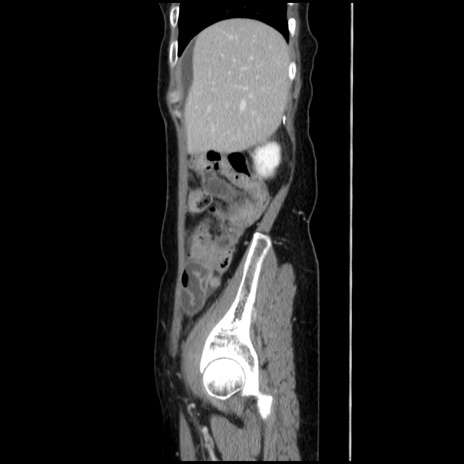

横断像